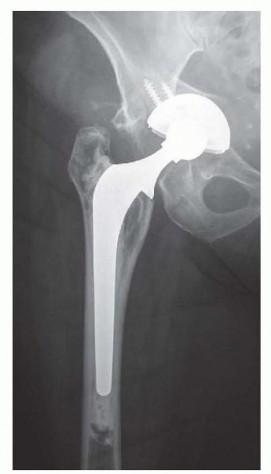

DEFINITION Acetabular bone deficiency may occur primarily (eg, dysplasia, inflammatory arthritis, or seronega…

Indications Relative indications for a cemented femoral stem include: Smaller, less active patients Dorr type…